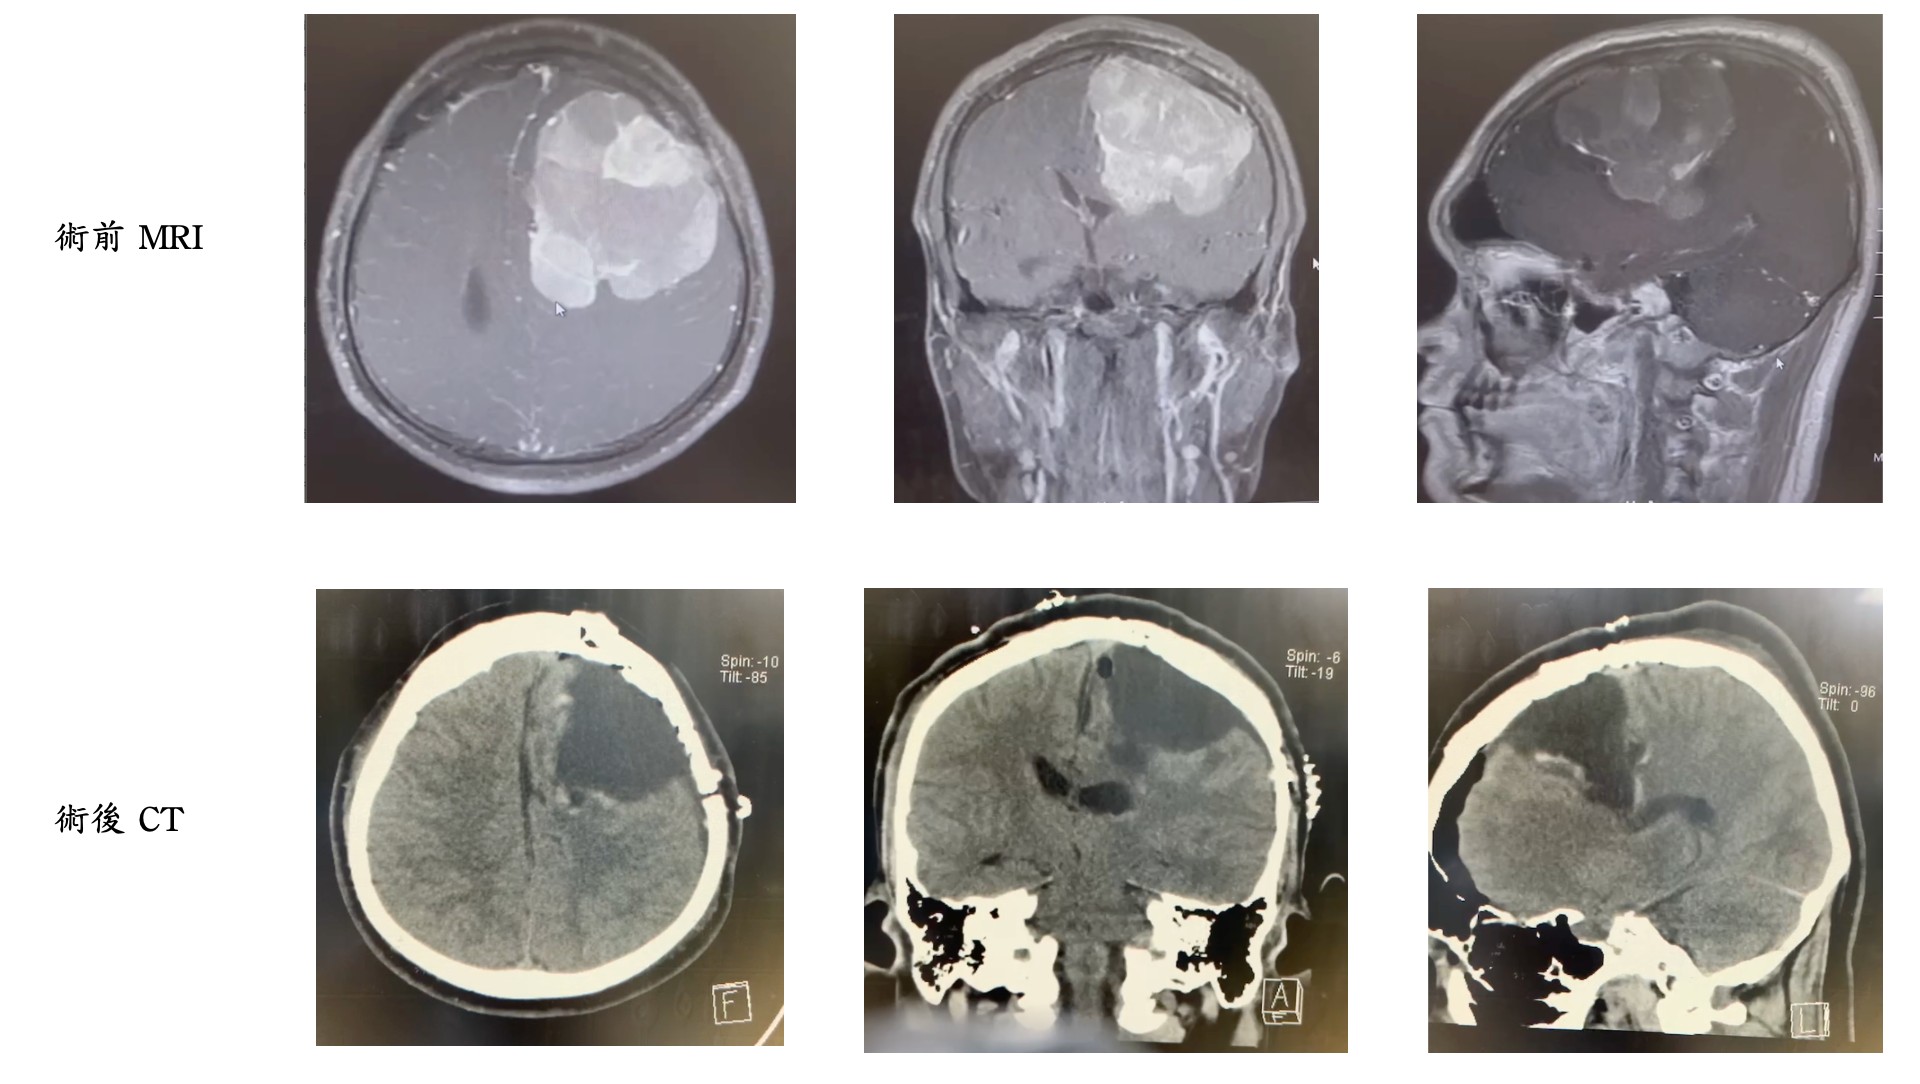

(腦瘤摘除手術前後對照圖)

王端靖醫師 解釋,透過CT(電腦斷層掃描)和MRI(核磁共振)檢查,他們發現李先生的腦腫瘤大小達7公分,且生長位置相當深,使手術視野變得狹小,這對於手術來說相當具挑戰性。為了縮短手術時間並考慮手術的複雜性,王端靖醫師 邀請了亞東醫院神經外科的蔡翊新主任 協助,最終由兩位醫師攜手成功完成手術。